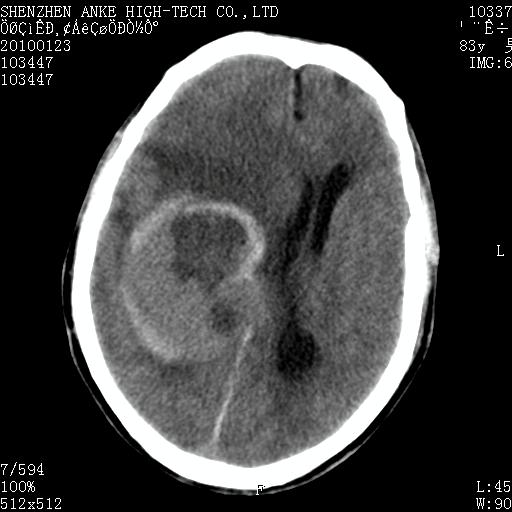

标题: CT24299:头颅平扫

患者:男,83岁,突发意思不清2天。原有脑梗塞病史。

肿瘤卒中,考虑恶性,依次淋巴瘤、转移瘤、恶性脑膜瘤、胶质母等,建议mri。

肿瘤卒中,考虑恶性脑膜瘤可能性大。

考虑脑膜瘤出血.

脑膜瘤多见于老年女性,与雌激素水平有关。本例虽为老年男性,但是本例还是考虑脑膜瘤的可能性大。

镰旁脑膜瘤卒中